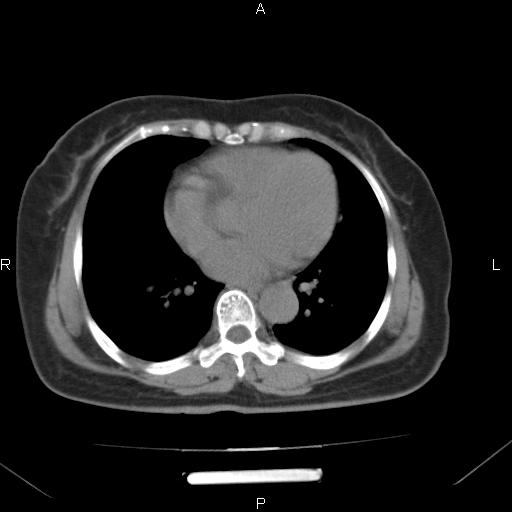

女、63Y 双眼睑下垂,早轻晚重。 胸腺瘤???

结果胸腺瘤